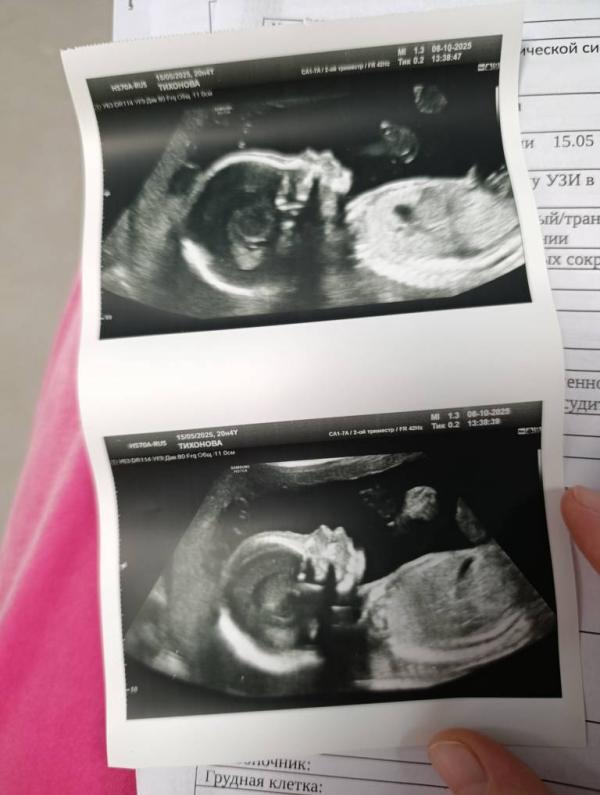

Вчера был 2ой скрининг,все в пределах нормы, всё хорошо,нет никаких рисков на сегодняшний день 🙏🏻🙌🏻я выдохнула, очень рада🥰 весим 330гр 20 недель)мамочки,а сколько у вас весили/весят малыши на 20 недель?🧐